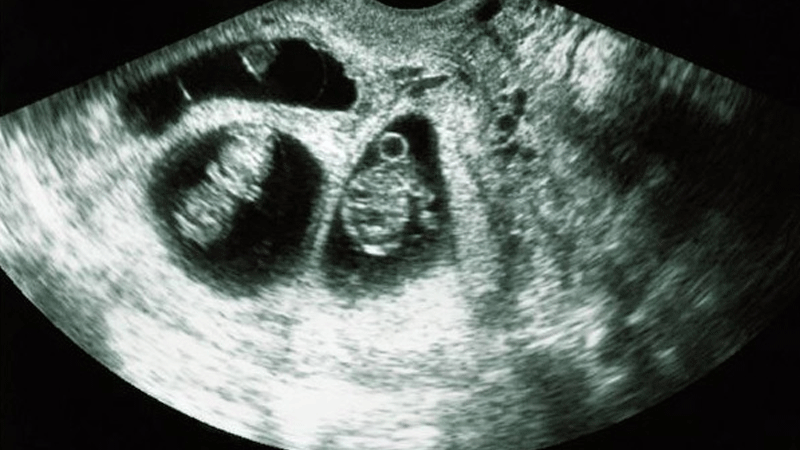

ووجد الأطباء، بواسطة عمليات المسح بالأشعة المقطعية، "الجنين المتحجر"، أو كما يعرف أيضا باسم "الجنين المتكلس" (lithopedion)، والذي كان موجودا في جسد والدته لمدة 56 عاما.

ويعرف "الطفل المتحجر" بأنه ظاهرة نادرة تحدث بداية من الأسبوع الـ 14 من الحمل، عندما يموت الجنين أثناء الحمل البطني، ويكون أكبر من أن يعاد استيعابه من قبل الجسم، وبالتالي يتكلس من الخارج كجزء من تفاعل غريب يحمي جسم الأم من النسيج الميت من الجنين ويمنع العدوى.